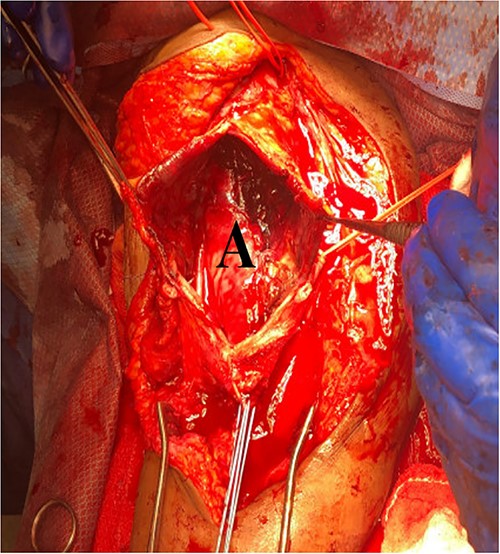

She then re-presented 2 months later with gradually increasing right upper extremity edema with a palpable thrill in the arteriovenous fistula. Duplex identified a large hematoma with patency of the fistula (Fig. 2). A tunneled dialysis catheter was placed to allow the swelling and hematoma to resolve. After medical optimization, the patient consented for operative intervention with the intention to evacuate the hematoma. There was noted to instead be a 20 × 35 cm PSA of the brachial artery (Fig. 3). The median nerve was identified and preserved. After proximal and distal control, the patient was heparinized, and the brachial artery PSA was decompressed with evacuation of large mural thrombi (Fig. 4). This artery segment was resected, and patch angioplasty was performed (Fig. 5). The fistula was ligated, and the distal remnant was preserved. Radial and ulnar pulses were palpable. The patient recovered well postoperatively.

Surgical measures in treating PSAs include resection, ligation, re-anastomosis, or vein graft interposition. Open surgery is indicated with rapidly expanding aneurysms, larger PSA size, rupture, distal ischemia, or neuropathy of the median nerve from local pressure [11]. Smaller arterial defects can be repaired with sutures or patch angioplasty [12]. Axillo-radial or axillo-ulnar bypass grafting with reversed great saphenous vein can be considered [9]. Saphenous vein interposition graft is preferred when the PSA is located at or proximal to the brachial bifurcation in order to maintain continuity and extremity viability [9]. PSA sac excision may also be performed with vascular continuity maintained with an end-to-end anastomosis between the brachial artery and interposition vein bypass graft [13].

We elected to perform pseudoaneurysmal resection and arteriovenous fistula ligation due to the large pseudoaneurysmal size. Often, patients with end-stage renal disease also lack quality autogenous vein for interposition grafting. Primary repair with bovine patch can be performed immediately without additional vein harvest time and is a viable option to avoid interposition grafting.